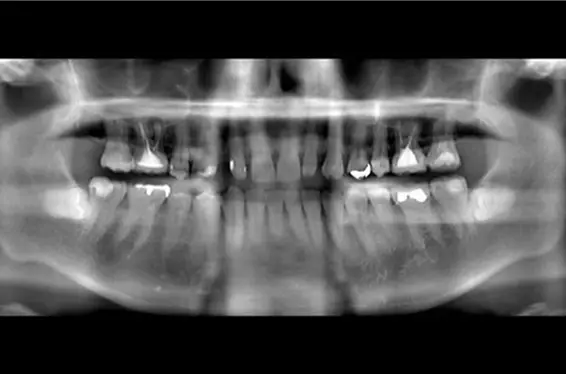

歯を失ったまま放置していると、噛み合わせや骨のバランスが崩れ、やがてお口全体に大きな影響を及ぼします。そのため、しっかりと噛める状態に回復することがとても重要です。

万が一歯を失ってしまった場合でも、インプラントは機能性と見た目の両面で非常に優れた治療法です。当院でも、多くのご要望に応じ、これまで数多くのインプラント治療を行ってまいりました。

• 治療内容:右上1、左上、歯根の破折により抜歯。大幅に骨か吸収していたために、1回目骨造成(こつぞうせい)(GBR)手術。4か月後、インプラント埋入手術。右上1番を支台とした、12本のインプラントブリッジの被せ物